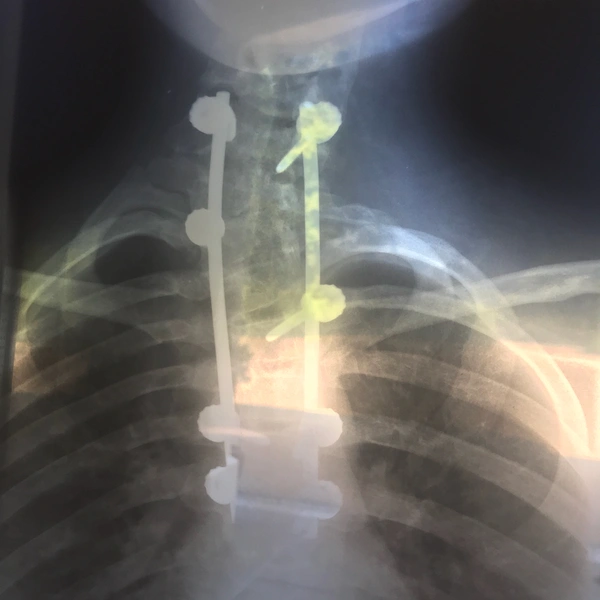

Принцесса Евгения — одна из немногих членов семьи Виндзор с собственным аккаунтом в Instagram (запрещенная в России экстремистская организация). На днях Ее Высочество решила опубликовать довольно необычный кадр — в блоге Евгении появился рентгеновский снимок ее позвоночника. Как выяснилось, не просто так: последняя субботу июня — День борьбы со сколиозом.

Так принцесса решила поделиться собственным опытом: в детстве у Евгении был диагностирован врожденный сколиоз. В 12 лет принцессе была проведена операция коррекции, в ходе которой ей установили корректирующие металлоконструкции. В одном из интервью Ее Высочество заметила, что они с ней «навсегда». Также принцесса опубликовала фотографии, сделанные во время посещения королевского национального ортопедического госпиталя.

«В Международный день борьбы со сколиозом я хочу впервые и с гордостью поделиться своими рентгеновскими снимками. Я также хочу выразить уважение потрясающим сотрудникам королевского национального ортопедического госпиталя, которые неустанно работают, спасая жизни и делая людей лучше, — пишет Евгения. — Они сделали лучше и меня, и я рада быть патроном их организации Redevelopment Appeal (ее цель — привлечение финансовых средств со стороны филантропов и благотворительных организаций на покупку оборудования — прим. ред.)».